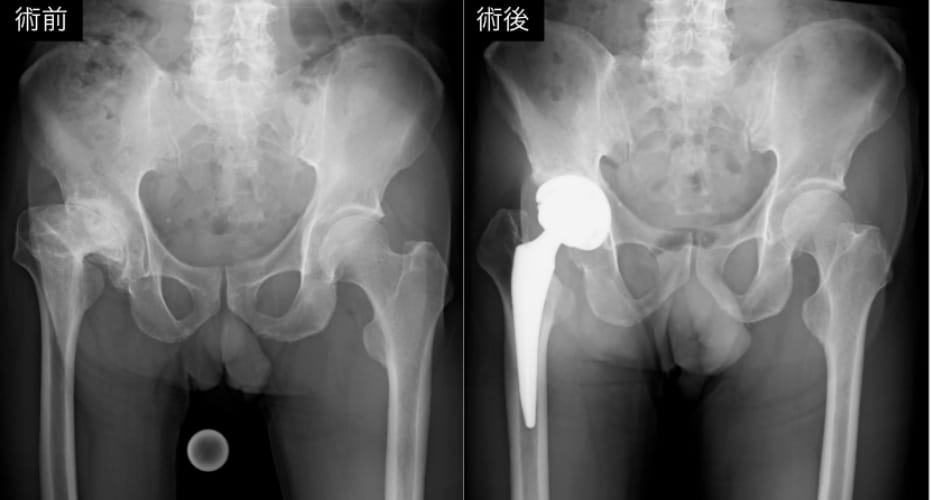

変形性股関節症に対する人工股関節置換術

変形性関節症や関節リウマチ、骨壊死などにより関節の疼痛や機能障害が高度となり、保存療法で十分な改善が得られない症例を適応として行っています。障害された関節を人工材料に置換することで、疼痛の軽減、可動域の改善、ならびに日常生活動作の回復が期待されます。股関節や膝関節に加え、肩関節、肘関節、足関節など幅広い関節に対して施行しています。特に股関節および膝関節では、術前計画に基づくインプラント選択と正確な設置が長期成績に重要であるため、ナビゲーションやロボットなどの手術支援技術を活用し、精密かつ個別化された治療を行っています。